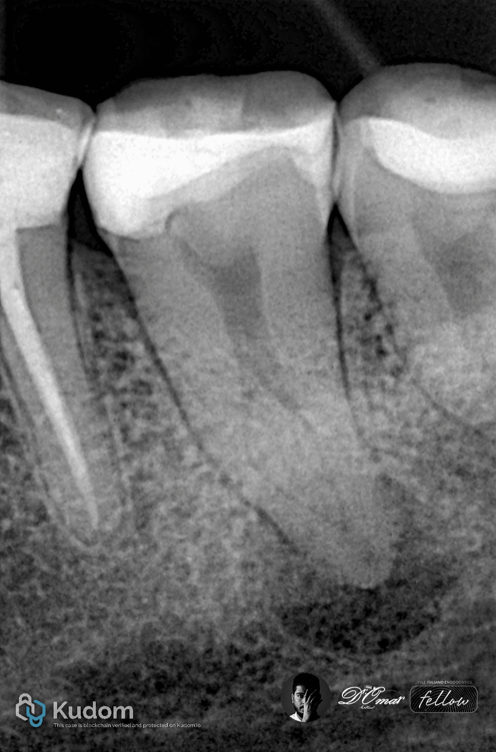

Fig. 1

Two-Canal Mandibular Molars

Two-canal mandibular molars typically consist of one mesial and one distal canal, often with round or oval cross-sections. These canals are usually wide, relatively straight, and accessible, allowing efficient mechanical shaping and irrigant penetration.

Radiographic examination showed a well-defined periapical radiolucency

Diagnosis

Necrotic pulp

Chronic apical periodontitis

Anatomy

Access revealed:

One mesial canal

One distal canal in one apical foramen